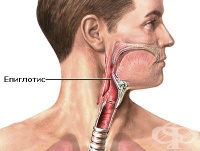

S10.8 Повърхностна травма на други части на шията

Повърхностно увреждане на епиглотиса при директен удар в областта на шията влиза в повърхностна трав...